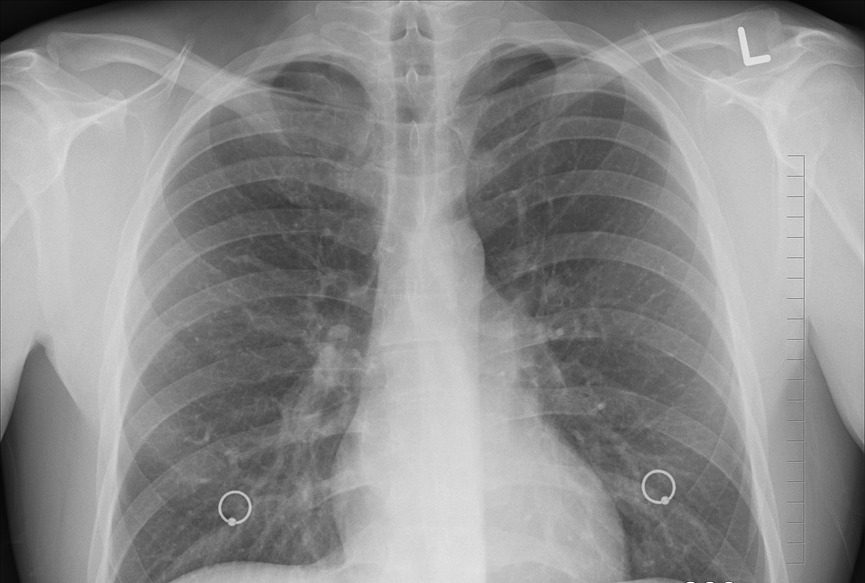

En 2018, el Globocan registró que el cáncer de pulmón sigue siendo la primera causa de muerte por cáncer a nivel mundial; sin embargo, uno de los mayores enigmas de México es que sus cifras de incidencia y muerte de cáncer de pulmón están hasta 4 veces por debajo de otros países con un desarrollo económico y social similar, explicó el doctor Alejandro Mohar Betancourt, titular de la Comisión Coordinadora de Institutos Nacionales de Salud y Hospitales de Alta Especialidad (CCINSHAE).

El doctor Mohar explicó en la Academia Nacional de Medicina que uno de los primeros pasos para resolver este enigma y poder tratar mejor a los pacientes con cáncer de pulmón, tanto a nivel curativo como preventivo, es conocer las tasas de incidencia y mortalidad, algo que hasta hace poco no había sido posible por la fragmentación tan grande en que se encuentra el sistema mexicano de salud.

“El registro sirve para definir políticas del control de cáncer en nuestros países. La propuesta en México es que este registro de cáncer fundamente el Plan Nacional de Cáncer y se tenga un programa de prevención y control de cáncer y, con ello, el diagnóstico temprano y un mejor tratamiento”, añadió el doctor Mohar.

Adicionalmente a esto, otra de las propuestas más recientes para bajar la tasa de incidencia y mortalidad de cáncer de pulmón en México es que el Instituto de Salud para el Bienestar, propuesto por el presidente de la República, Andrés Manuel López Obrador, como sustituto del Seguro Popular, atienda al 100 por ciento los casos de cáncer de pulmón, cosa que el Seguro Popular no hace pues no cubre el tratamiento por este neoplasia.

“Hay poca información epidemiológica y urge un diagnóstico temprano”, concluyó el doctor Mohar. (FORO CONSULTIVO CIENTÍFICO Y TECNOLÓGICO A.C)